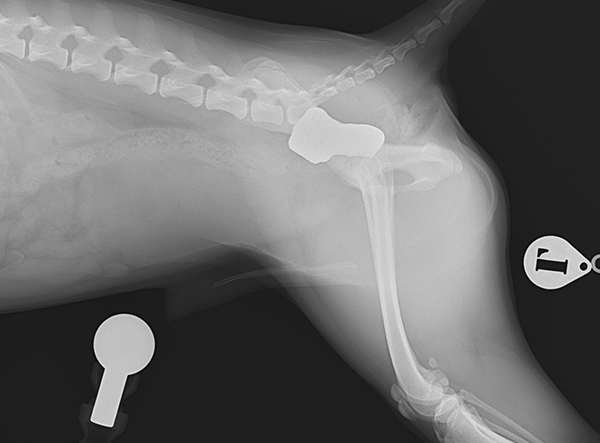

In July 2025, a tiny Shiba Inu weighing only 5.8 kg underwent a pioneering procedure for bilateral hip dysplasia — becoming one of the smallest dogs ever to receive a 3D HIP Implant Implant by Rita Leibinger.

The surgery involved implanting a 2.4 mm 3D HIP Patient-Specific Implant (Titanium) to address severe bilateral hip dysplasia. According to Prof. Dr. Björn Meij (Utrecht University), this miniature Shiba Inu represents the smallest patient on Earth to have successfully undergone this advanced orthopedic procedure. The precision and adaptability of the 3D HIP system allowed for a stable and minimally invasive intervention, tailored to the patient’s unique anatomy.